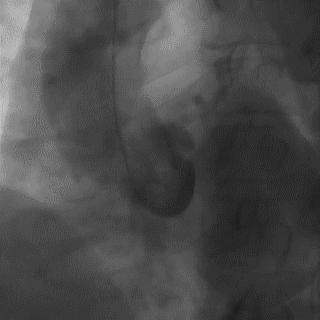

2014年,Patel T等首先采用球囊辅助通过技术(Balloon-assisted tracking,BAT),用于通过桡动脉途径中扭曲、细小节段(包括严重痉挛节段)(图1-2)。

图1

图2 BAT技术应用实例1。52岁女性患者冠脉严重痉挛(A),注射2次鸡尾酒后仍未缓解(B),采用BAT技术(C),顺利介导7F指引导管通过桡动脉严重痉挛节段(D)